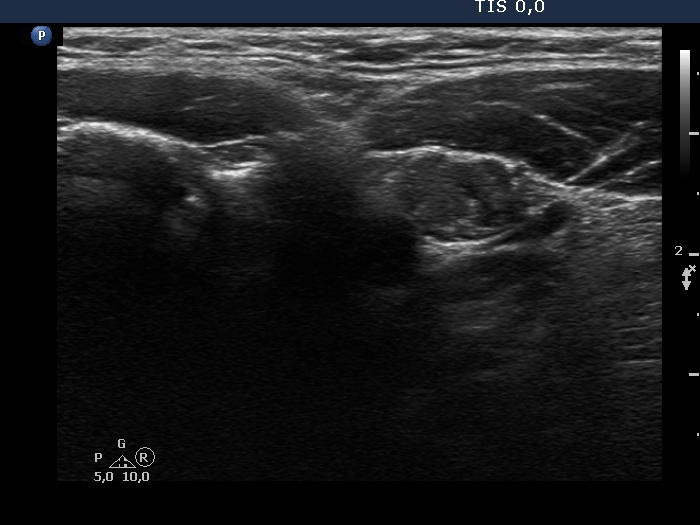

Ultrasonography. The thyroid was echonormal. There were two nodules in the left lobe. The upper lesion was a dominantly isoechoic nodule which had microcalcifications while the lower one was a hypoechoic nodule. There were numerous microcalcification relatively far from the primary tumor focus. The upper nodule was avascular while the lower one presented both intranodular and perinodular blood flow.

A conglomerate of lymph nodes was found 2 cm above the left lobe. The nodes did not have hilum but contained microcalcifications and presented irregular vascular pattern. (This was not noticed on the previous ultrasound examination.)